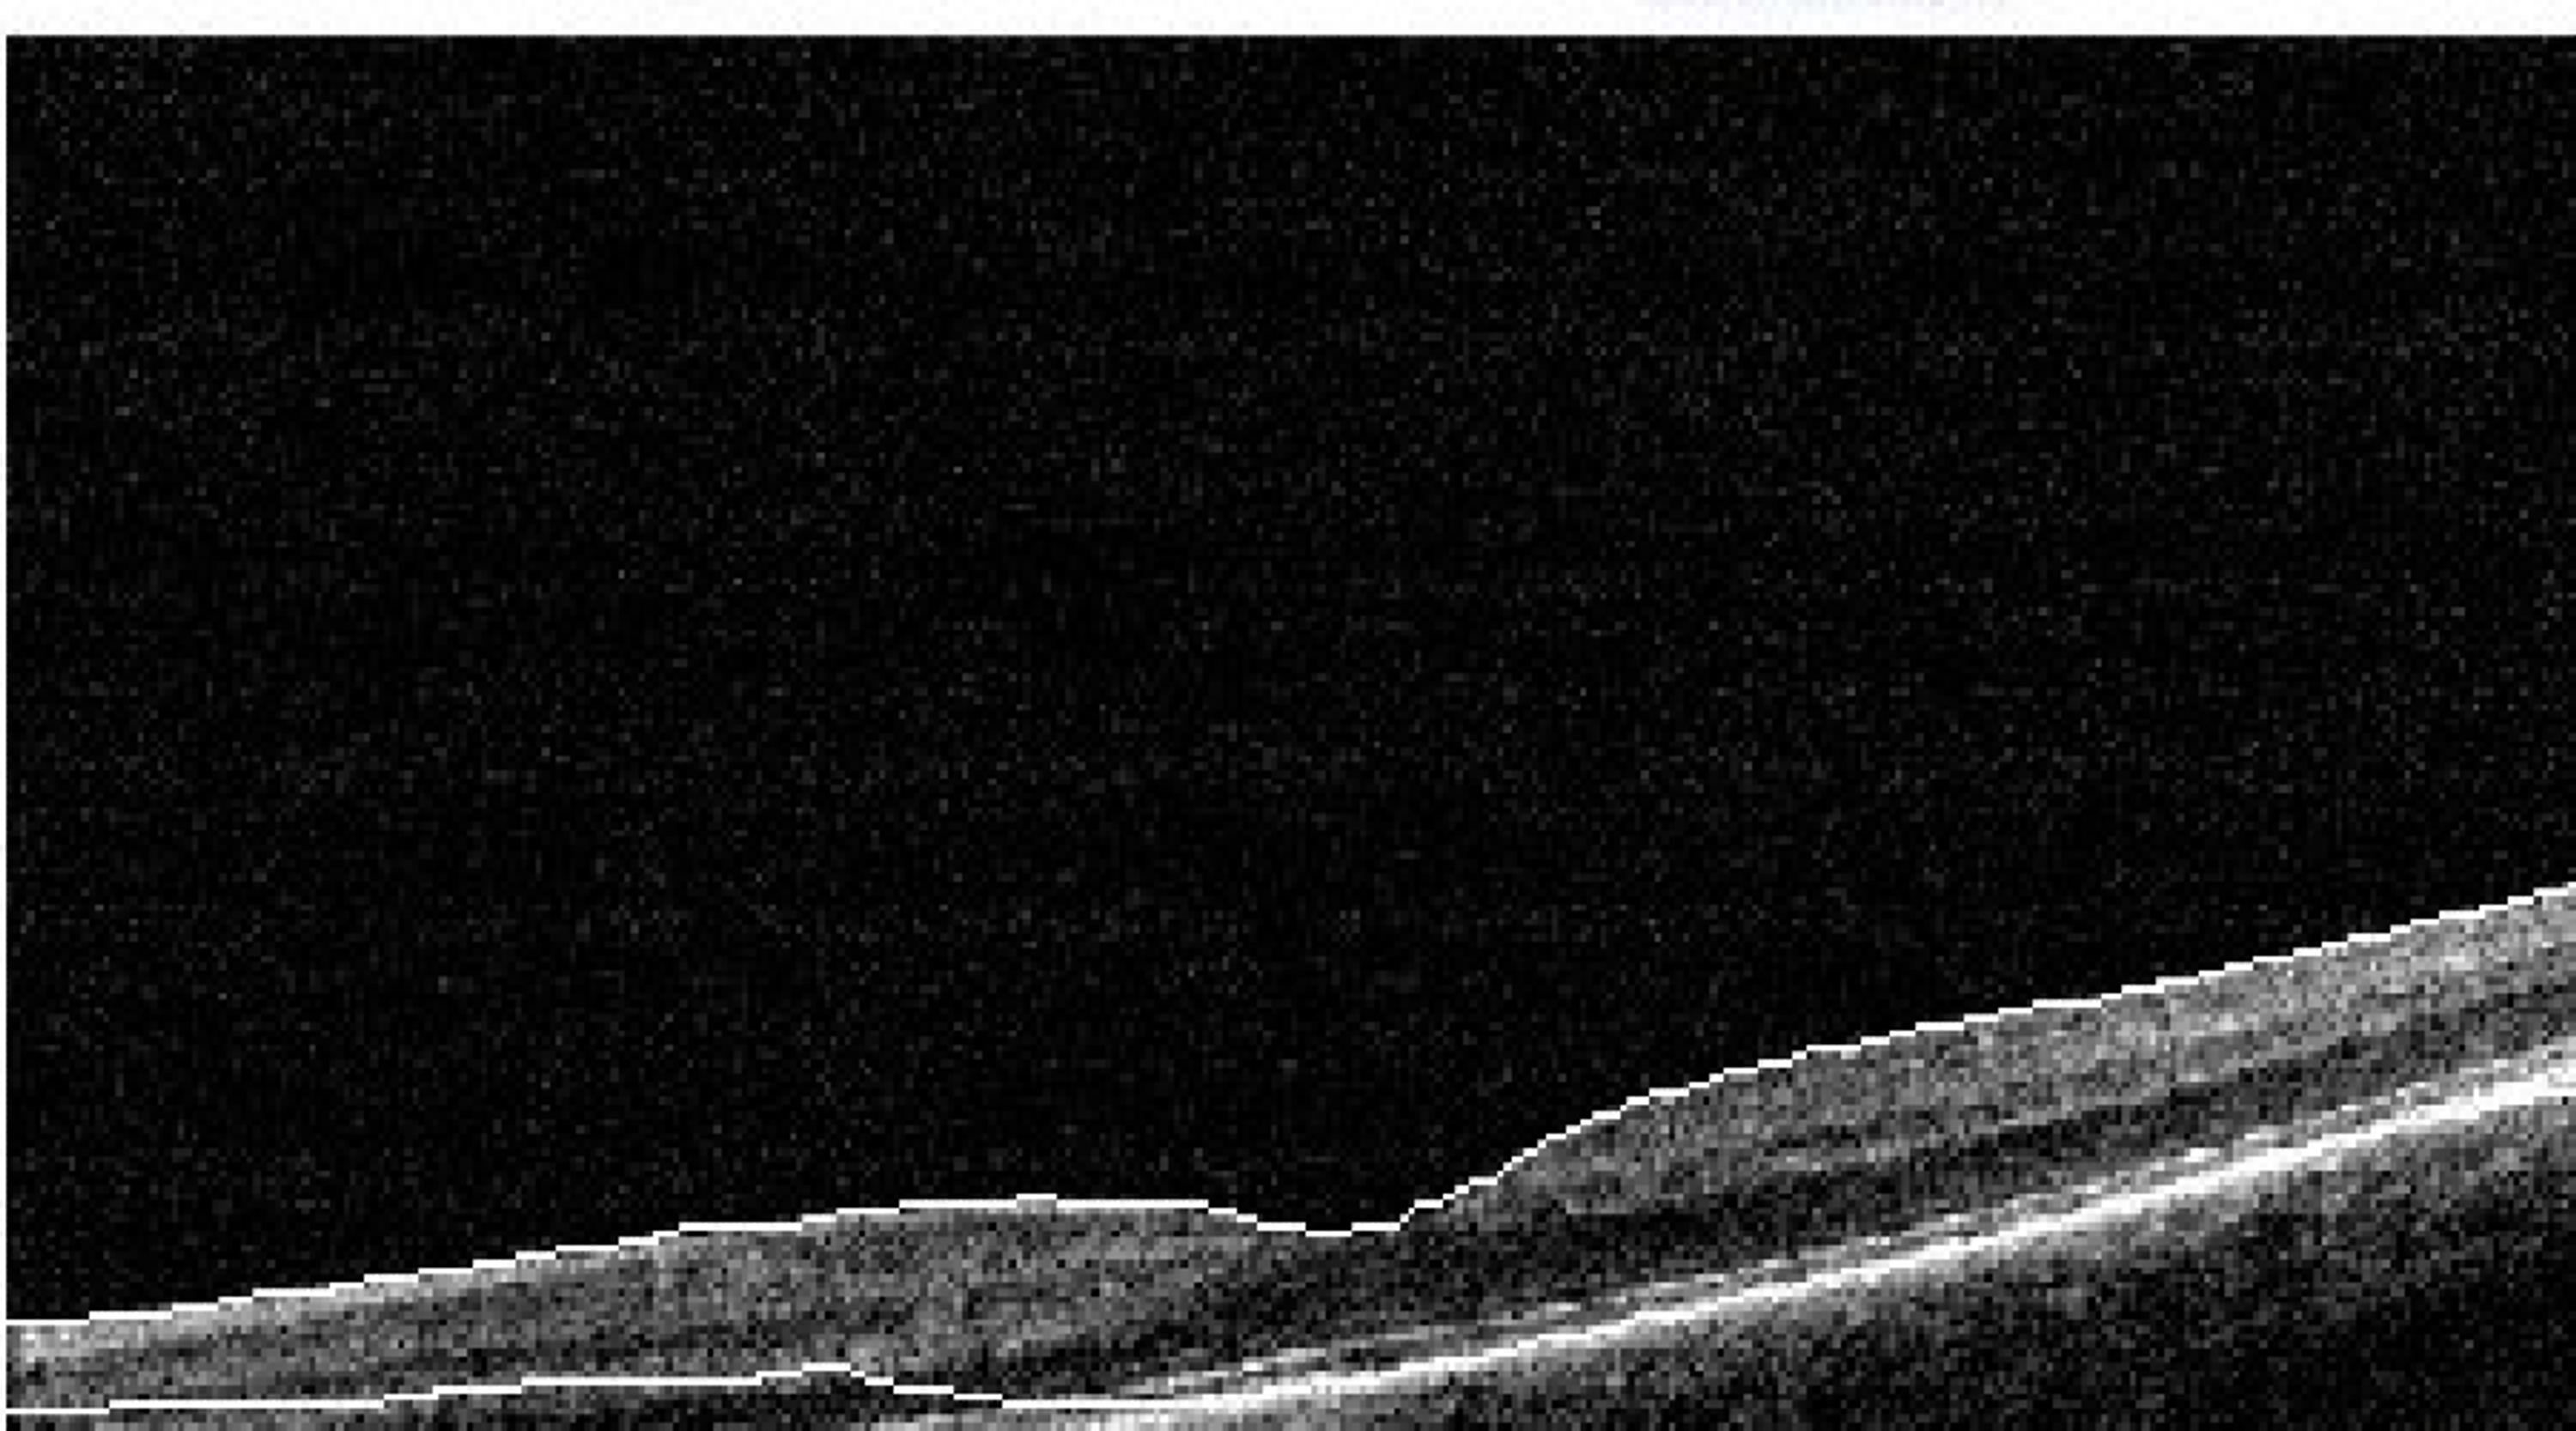

From en.octclub.org

Laser Induced MaculopathyAugust 2021 OCT Club Laser Pointer Maculopathy Treatment based on time to presentation after the laser injury, the patients were divided into two groups: Retinal injury in a teenage boy and laser pointers. commercial handheld laser pointers may inflict notable macular injury and damage vision permanently. In the past, laser pointers sold to the public had a. An early group comprising those who presented within a. Laser Pointer Maculopathy Treatment.